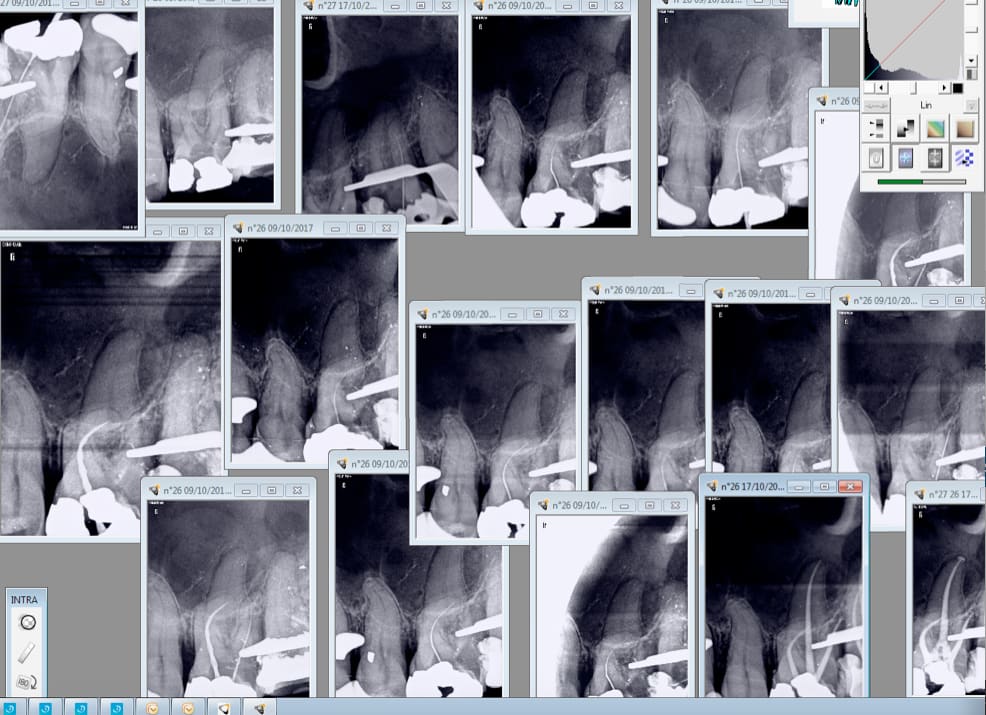

Danger public le chicot. Une vingtaine de clichés à 0,09 S et 70 KV. Vaut mieux pour le patient une peinture canalaire et 2 clichés , une pré et post op argentiques ( Plus d'une seconde le cliché) que tu développes quand tu as le temps ?

un CBCT coute aujourd'hui 60Ke donc , grosso modo 1000 euros par mois (deductibles) ... imaginons un confrere qui ferait 200 endos par an (ce qui est un minimum) qui ne facturerait aucun CBCT à ce titre ,et qui prendrait un cinquantaine de clichés "justifiés" facturés par an ; le surcoût du CBCT de l'acte globalisé par endo + prothèse serait de 30 euros

pour une augmentation de qualité phénoménale , et une facilité de localisation et de préparation des canaux inimaginables ; donc une productivité améliorée d'une manière considérable

mais , c'est vrai , certains d'entre nous n'ont besoin que de leurs doigts pour determiner une longueur de travail contrairement aux pauvres couillons comme moi qui sommes contraints de prendre des mesures physiques

certains trouvent systématiquement le 2e MV grace à leur seul instinct, d'autres encore visualisent les canaux biphydes sagitaux ou triphydes des prémolaires etc ... ceux-la sont des artistes ... moi non ; je suis un besogneux : j'ai besoin de représentation tridimensionelles pour comprendre certaines particularités anatomiques .